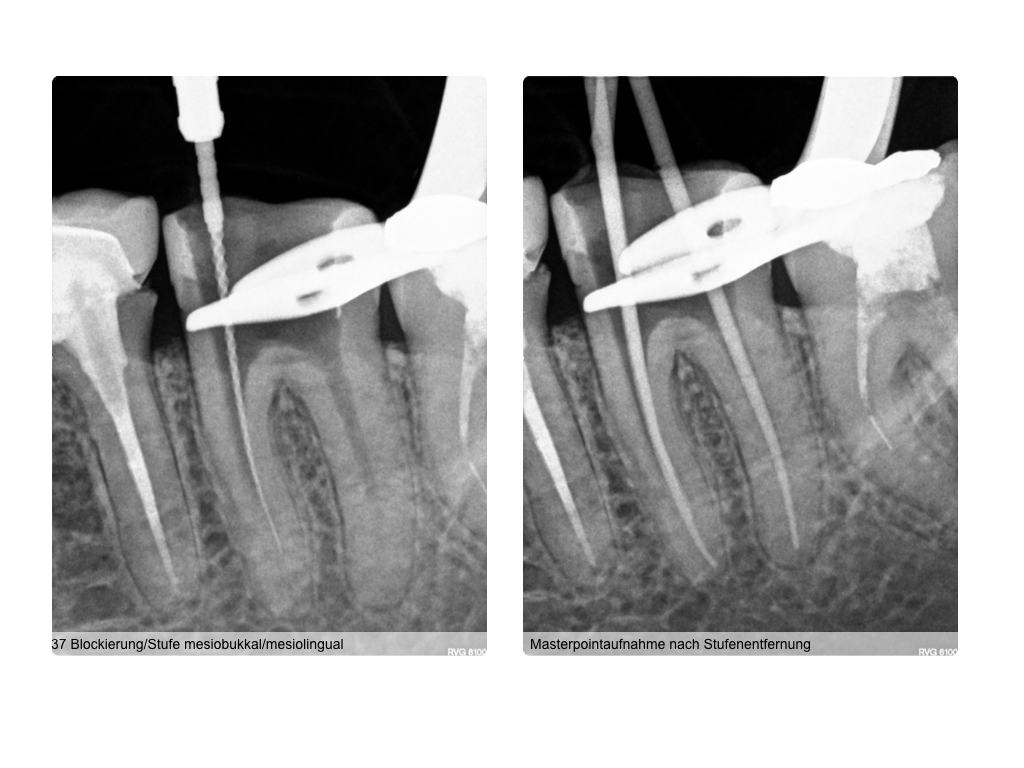

wsi-122016-016

4 auf einen Streich (2)